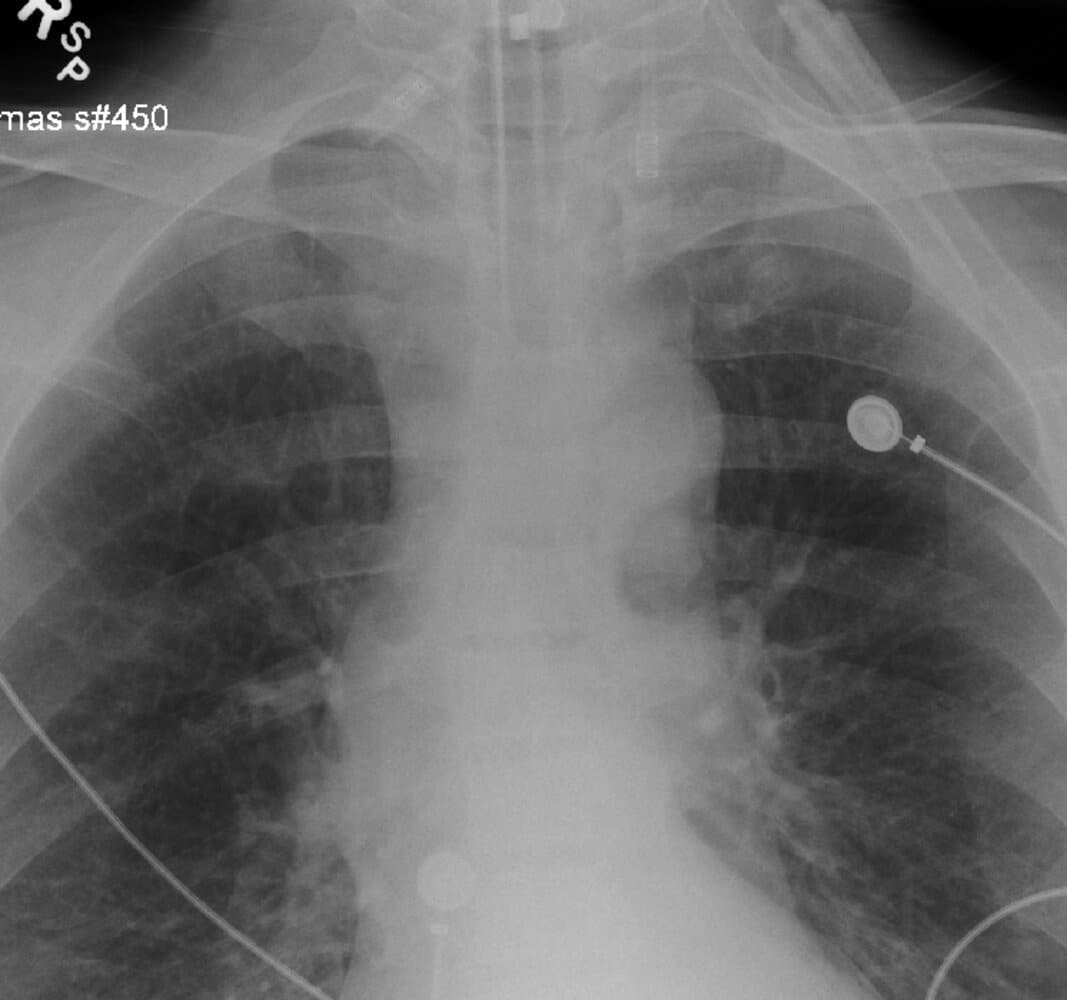

After performing these procedures, a chest X-ray can be used to confirm the ET tube positioned just above the carina. However, obtaining an X-ray to confirm placement must not interfere with the resuscitation process.

X-Ray view of ET tube properly placed above the carina

X-ray view of right mainstem intubation with white markings on the left chest indicating no air movement